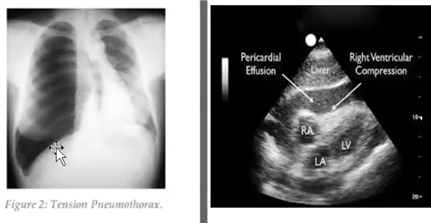

• Obstruktiv chock

• Massiv lungemboli

• Övertryckspneumothorax (bild)

• Hjärtamponad (bild)